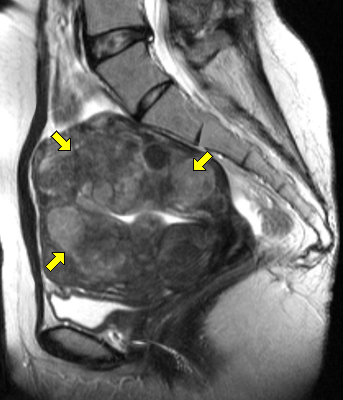

MRI 영상: 자궁 내에 여러 개의 커다란 자궁근종들이 보임